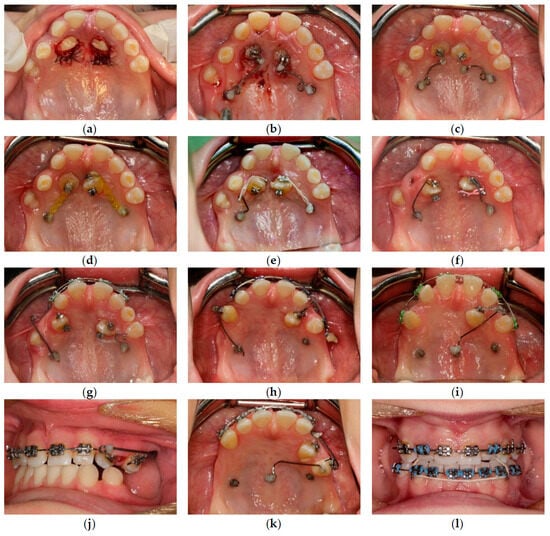

| October 2017 | PDCs’ surgical exposure—open technique; brackets bonded on PDCs; MIs tomas®-pin SD 06 (Dentaurum, Ispringen, Germany) inserted in the palatal alveolar region; 0.016″ × 0.022″ TMA cantilevers activated in distal and downward direction (50 g) (Figure 6a,b). |

| November 2017 | Visible orthodontic movement—exclusion of primary ankylosis (Figure 6c). |

| December 2017 | Increased mobility and tenderness of PDCs, dismantlement of cantilevers, button on the buccal side of UL3 (derotation), power chains to move the teeth (Figure 6d). |

| January 2018 | Teeth stability improved; 0.017″ × 0.025″ TMA cantilever with activation in downward and buccal directions for UR3, power chain for distal movement and derotation of UL3. |

| February 2018 | Button on the buccal side of UR3 (derotation), power chains for distal movements and derotations (Figure 6e). |

| April 2018 | Extraction of the upper right deciduous canine due to the collision with movement of UR3; 0.017″ × 0.025″ TMA cantilever activated for buccal movement of UR3 (50 g) (Figure 6f). |

| June 2018 | Partial fixed upper SS appliance Equilibrium® 2 0.022″ in Roth prescription (Dentaurum, Ispringen, Germany), 0.016″ NiTi wire, continuous metal ligature to create space for UL3; cantilever activation (Figure 6g). |

| August 2018 | Bracket on tooth no. 24; 0.016″ NiTi wire and open coil spring to create space for UL3; extraction of the upper left deciduous canine. |

| October 2018 | New MI tomas®-pin SD 08 (Dentaurum, Ispringen, Germany) was inserted in the buccal surface of left alveolar ridge; 0.017″ × 0.025″ TMA cantilever for buccal movement of UL3 (50 g) (Figure 6h). |

| November 2018 | Mobility of the buccal alveolar MI, the miniscrew was tightened and left to stabilize for a month; tooth no. 55 was extracted due to progressive reinclusion. |

| December 2018 | Buccal alveolar MI was lost and new MI tomas®-pin SD 10 (Dentaurum, Ispringen, Germany) was placed in the IZC; 0.017″ × 0.025″ TMA cantilever with buccal activation for UL3 (50 g). |

| February 2019 | Inflammation and submucous abscess in the IZC; MI removal; antibiotic. |

| April 2019 | New MI tomas®-pin SD 10 (Dentaurum, Ispringen, Germany) was inserted in the palatal suture and used as a direct anchorage with 0.017″ × 0.025″ SS cantilever and power chain for buccal movement of UL3 (50 g); 0.016” SS wire and bend-out for UR3 (Figure 6i). |

| May 2019 | Overcorrection of UR3 transversal relationship, 0.018″ SS wire and bend-out for tooth no. 22, new power chain from cantilever to UL3 for its buccal movement. |

| July 2019 | Tooth no. 22 in correct sagittal relationship; MI in the palatal suture used as an indirect anchorage: 0.017″ × 0.025 SS connection wire with tooth no. 24, 0.017″ × 0.025″ cantilever with buccal activation for UL3 (50g); 0.017″ × 0.025″ Cooper NiTi wire (Figure 6j,k). |

| March 2020 | The correct position of UL3; tooth no. 24 showed significant mobility; control panoramic X-ray: root resorption of tooth no. 24 (Figure 7); no possibility to conduct control visits on a regular basis due to COVID-19 pandemic—next appointment took place in November 2020. |

| November 2020 | 0.019″ × 0.025″ SS wire, torque expression, closure of spaces with power chain. |

| March 2021 | Removal of MIs, 0.021″ × 0.025″ TMA wire for torque expression in the upper arch; Fixed lower SS appliance Dentaurum Equilibrium® 2 0.022″ in Roth prescription (Dentaurum, Ispringen, Germany); 0.016″ NiTi wire; elastics 4 ½ oz. from palatal buttons on teeth no. 12 and 22 to the lower arch to correct the anterior crossbite (Figure 6l). |